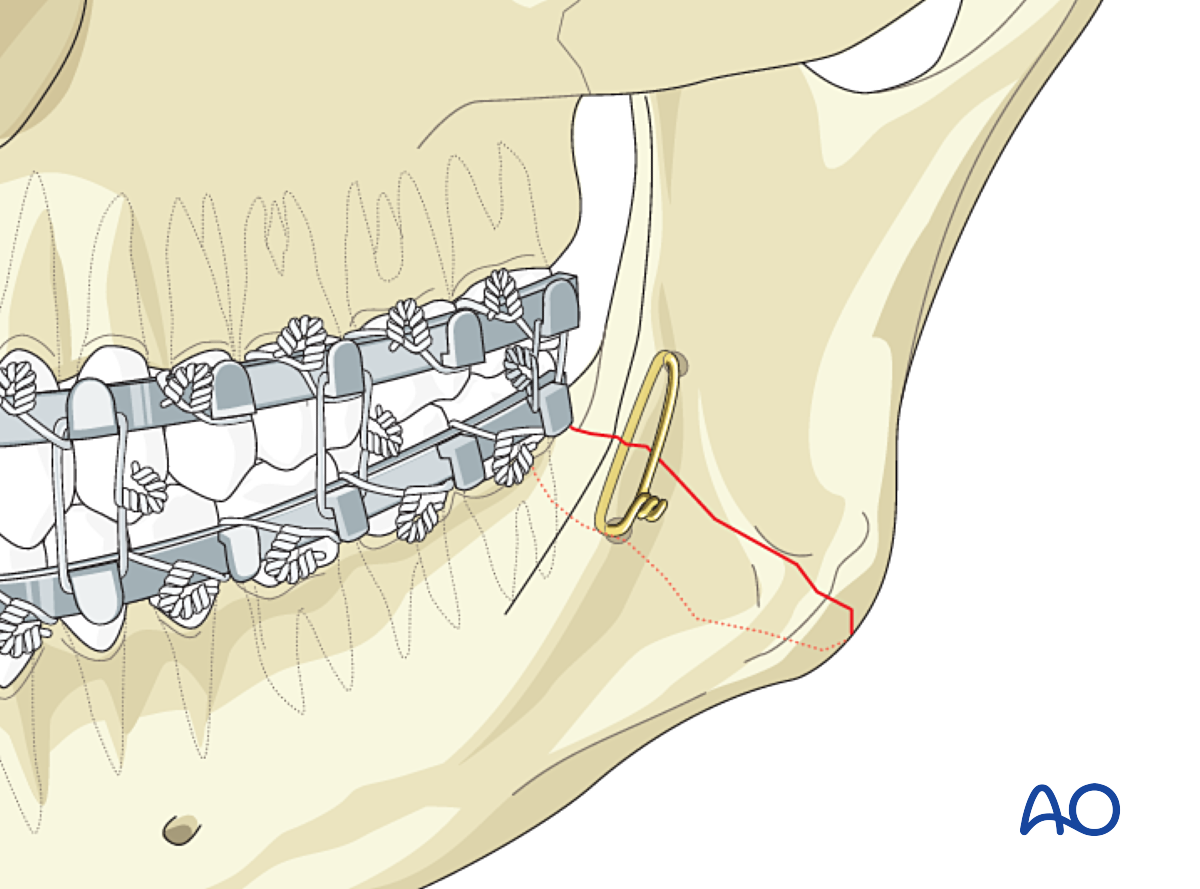

Остеосинтез скуловой

Остеосинтез скуловой 90 фото